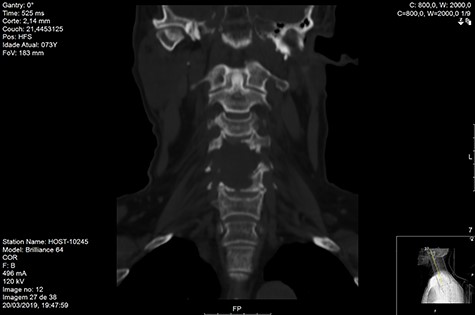

MRI and CT scans performed at 90 days post-radiation therapy showed an arrest of further progression of instability and resolution of the lytic lesion (Figs 7–13).

Although cases need to be discussed individually and surgery considered in cases of significant spinal instability or deformity and potential neurological injury, our results on this case supports the fact that isolated radiotherapy should be considered and be used to treat even extensively destructive osteolytic MM lesions to restore the structural integrity of the spinal elements.